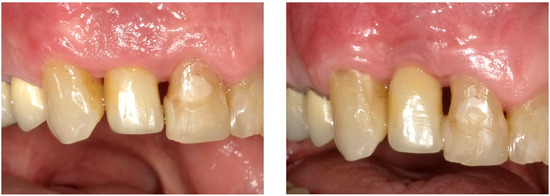

| Tpre | T12 | Tpre | T12 | Tpre | T12 | |

| Mesial papilla | 1 | 1 | 0 | 0 | 2 | 2 |

| Distal papilla | 1 | 1 | 0 | 0 | 2 | 1 |

| Curvature of the facial mucosa | 1 | 1 | 2 | 2 | 1 | 2 |

| Level of the facial mucosa | 0 | 2 | 2 | 1 | 1 | 2 |

| Root convexity/soft tissue color and texture | 0 | 1 | 2 | 2 | 0 | 1 |

| Total | 3 | 6 | 6 | 5 | 6 | 8 |